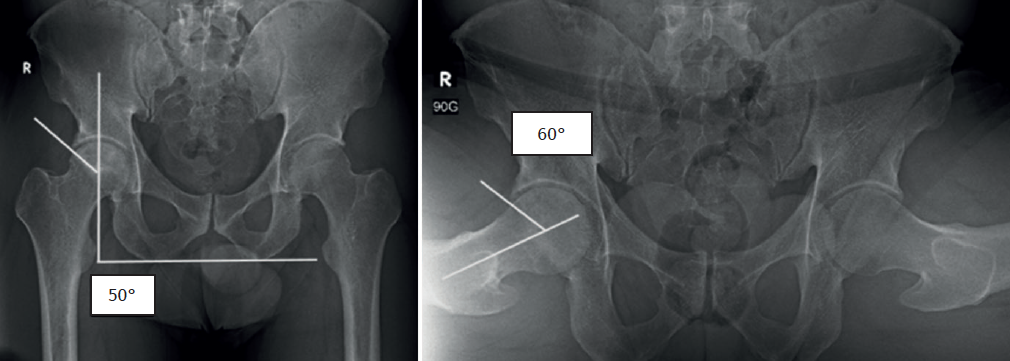

En el control a los 4 meses posquirúrgicos el paciente presenta una escala funcional HOS de 61/68 puntos (89,7%) y EVA de 0/10. En las pruebas de imagen se evidencia disminución de la zona de necrosis en la cabeza femoral mejorando el ángulo de Kerboul de 284° a 240° (Figuras 9 y 10). También se presentó como complicación una osificación heterotópica con una imagen de 0,8 cm de diámetro extraarticular proximal al cuello femoral.

Una limitación de este estudio es el corto seguimiento. Si bien el objetivo del presente artículo no es reportar resultados, nos permite describir una técnica quirúrgica reproducible, además de presentar el caso del paciente tratado y sus estudios imagenológicos de control, que nos posibilitan demostrar una disminución del ángulo de Kerboul a pesar del corto tiempo posquirúrgico, pasando de un riesgo alto de colapso a moderado. La mejoría clínica puede deberse a 2 factores. El primero es que se trataron patologías concomitantes en el mismo procedimiento (pinzamiento femoroacetabular y reparación labral) y el segundo factor es que, a pesar de no tener una ausencia completa del foco de necrosis en los estudios de imagen a los 4 meses, podemos tener neovascularización y formación de nuevas trabéculas óseas que han permitido que el colapso no se presente.

Figura 1. Radiografía anteroposterior (AP) de pelvis y proyección de Dunn a 90°, evidenciando un ángulo centro borde (Wiberg) aumentado de 50° y un ángulo alfa aumentado de 60°.